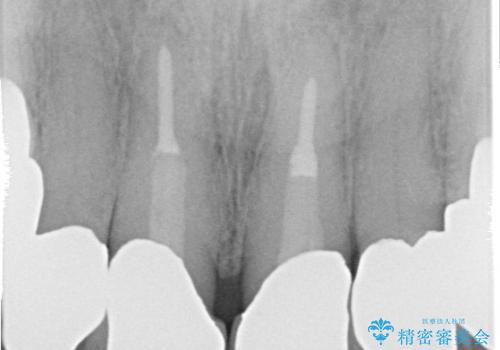

- 奥歯がなくて咬めないのと、全体的に見た目をよくしたいとのことで来院されました。

下顎の両側の奥歯が欠損しており、入れ歯をお持ちでしたが、うまく咬めずにほとんど使用していない状態でした。

上顎は全体的にクラウンの入れ替えと、下顎はインプラントの提案もしましたが、希望されなかったのでノンクラスプデンチャーの製作をする治療計画としました。

奥歯が欠損しており、上下の前歯が強く咬合する可能性があったので、上顎前歯の裏側は金属のものにしました。